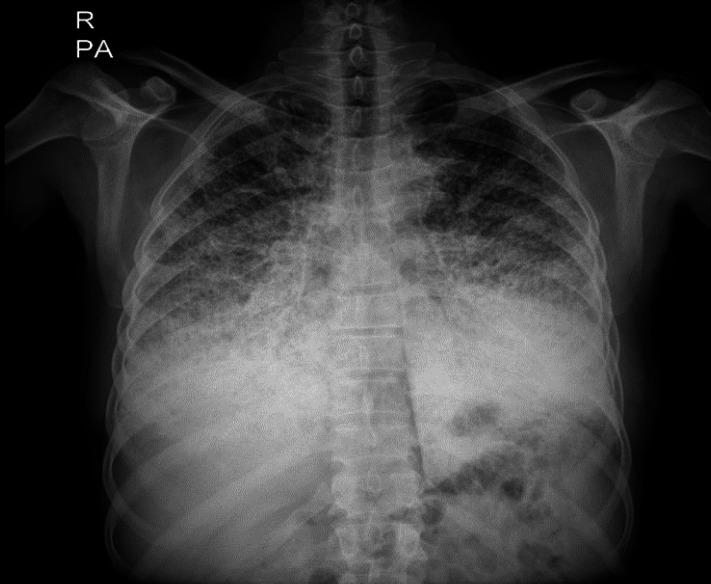

Herein, we have reported a 50-year-old male presented with recent sore throat, fever, and sweating. Radiological findings revealed bilateral micronodular pattern with diffuse ground glass attenuation in lower regions. Subsequent histologic examination of lung biopsy confirmed intra-alveolar accumulation of calculi and the diagnosis of PAM. In addition, we reviewed the literature narratively to clarify different aspects of PAM.

在此,我们报告了一名50岁男性,近期出现咽痛、发热和出汗症状。影像学检查发现双肺下叶有微结节影伴弥漫性磨玻璃影。随后的肺活检组织学检查证实肺泡内有结石堆积,确诊为PAM。此外,我们对相关文献进行了叙述性综述,以阐明PAM的不同方面。

In this paper, we presented a sporadic case of PAM which was suspected with chest x-ray and confirmed by HRCT and trans-bronchial lung biopsy. We hope that it can help clinicians to be more aware of this condition and make proper diagnosis.

本文报告了一例散发的PAM病例,通过胸部X线检查怀疑,经高分辨率CT(HRCT)和经支气管肺活检确诊。我们希望这能帮助临床医生更好地认识这种疾病并做出正确诊断。